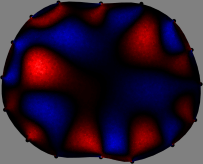

Figs. 3 and 4 compare the performance of the proposed FER method in (20) with the standard regularized least-squares method ((19) when is the identity matrix). The regularization parameter of the standard method was heuristically chosen for its best performance, and the parameter of the FER method was set to be one of three different values . The injection current was 1 mA at 100 kHz, and the frame rate was 9 frames per second. The reference frame at was obtained from the maximum expiration state. The measured data, , represent the voltage differences between each time and . The blue regions, which denote where conductivity decreased by inhaled air, increased during inspiration and decreased during expiration. The FER method with was clearly more robust than the standard method that produced more artifacts originated from the inversion process.

| Standard | |

||||||||||

| FER () | |

| FER () | |||||||||||